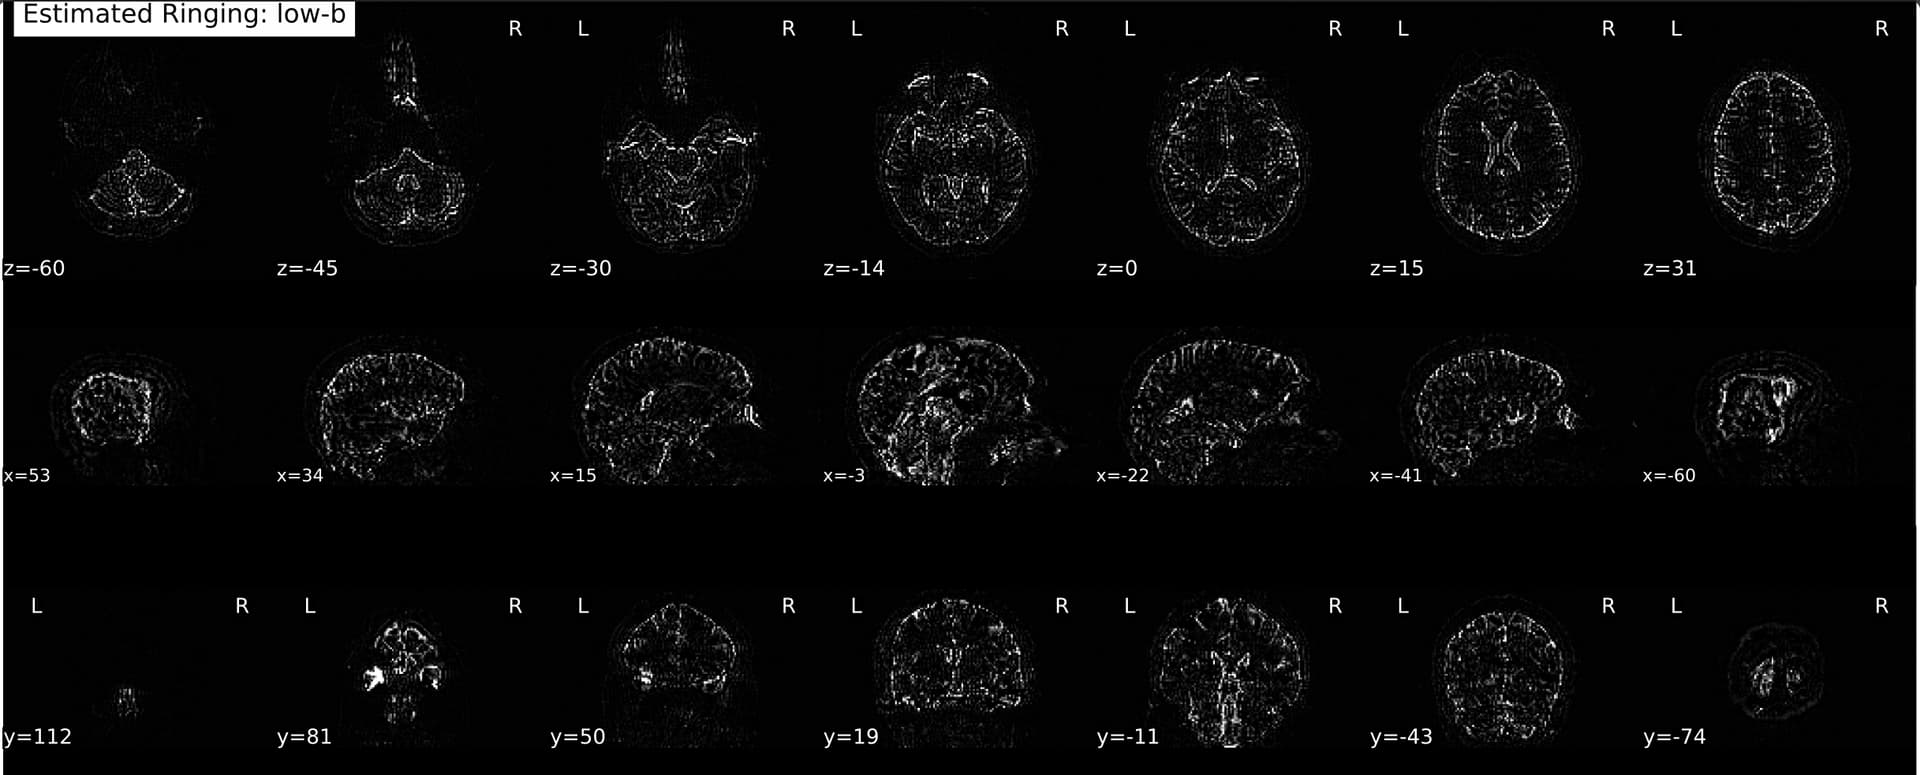

And it’s also not a plotting bug, as I can reproduce the visual report by manually subtracting: sub-x_dwi_LPS_denoised_unrung.nii - sub-x_dwi_LPS_denoised.nii.gz

So I thought maybe it might have something to do with running dwidenoise first—went and tested out RPG on a couple raw scans (no reorenting to LPS or MP-PCA, just run locally on my machine via the TORTOISE Docker container), and much to my surprise…

It switched! Now the cutoff is a bit more rostral along the PE axis and it’s just the posterior portion of the brain that seems to have estimated/removed Gibbs artifacts. Here’s an example from a cs-DSI collected in May of this year (absolute value overlaid after subtracting the first raw and unrung b=0 volume):

And one using the Q4 sampling scheme (same site but prior to a gradient coil replacement):